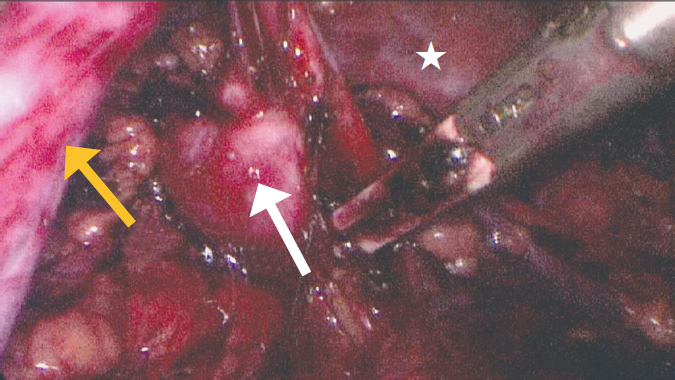

Fig. 4. Intraoperative view of a partially exposed atretic ureter (indicated by an asterisk). The arrow indicates the round ligament of the uterus, at the level of which atresia was visualized

Рис. 4. Интраоперационный вид частично выделенного атрезированного мочеточника (звездочка). Стрелкой указана круглая связка матки, на уровне которой визуализировалась атрезия

Fig. 5. View of the isolated hypoplastic lower segment of the doubled right kidney (indicated by a white arrow). The upper segment is indicated by an asterisk, the atretic ureter of the lower segment is indicated by a yellow arrow

Рис. 5. Вид выделенного гипоплазированного нижнего сегмента удвоенной правой почки (белая стрелка). Верхний сегмент указан звездочкой, атрезированный мочеточник нижнего сегмента — желтой стрелкой

The patient was admitted to the operating room with a diagnosis of cystic pelvic lesion. Laparoscopic isolation of the mass with the pelvic part up to 10 × 7 × 5 cm showed that it ended blindly at the level of the round ligament of the uterus (Fig. 2–4). As the cystic mass was isolated more proximally, its tight attachment to the right ureter, stenosis, and extension towards the kidney were noted. The right kidney and its hilum were accessed, and the cystic lesion was found to be an atretic, highly dilated ureter of the lower segment of the duplex right kidney (Fig. 5). Its inferior segment was hypoplastic, measuring up to 12 × 10 × 10 mm, with virtually no parenchyma. Therefore, it was decided to perform an inferior heminephroureterectomy. The final view and schematic presentation of the extracted mass are shown in Figure 6 and Figure 7, respectively. The postoperative course was uneventful. The patient had no active urinary tract infections. Laboratory parameters of renal metabolism were normal, and early postoperative ultrasound showed no abnormalities in the remaining right upper kidney.